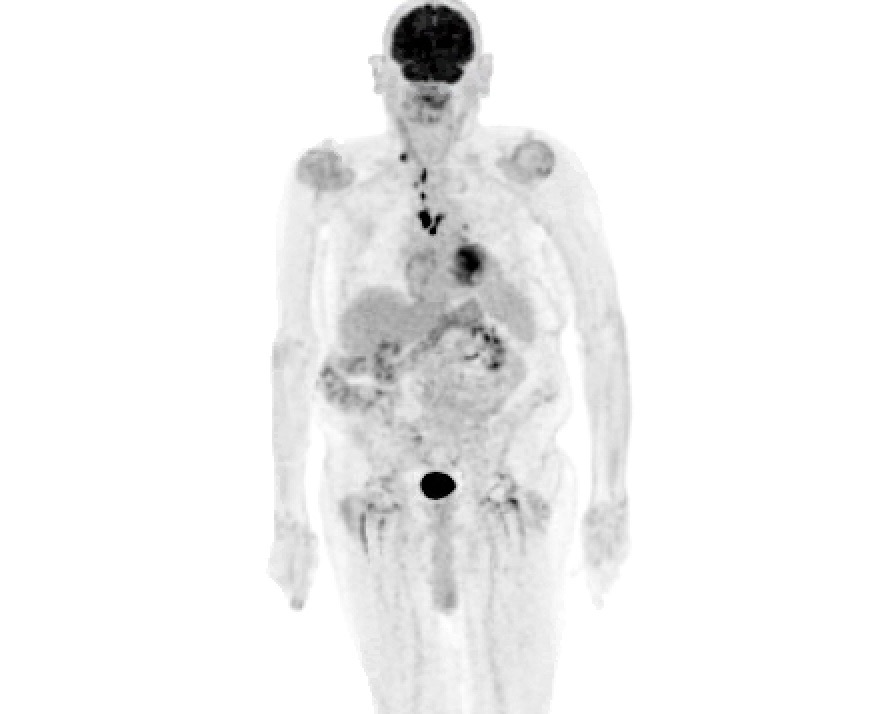

Treatment and management. Positron emission tomography (PET) at the time of diagnosis was suspicious for metastatic disease to the bowel and inguinal lymph nodes (Figure 3), so the patient began immunotherapy with pembrolizumab 200 mg every 3 weeks for 3 months.

Figure 3. Staging PET scan of the case 2 patient before treatment with two subcutaneous nodules along the bowel posteriorly, as well as a hypermetabolic right inguinal lymph node.

Outcome and follow-up. The patient completed four cycles of pembrolizumab, at which point a PET scan was repeated to assess response. The PET scan 5 months after diagnosis showed multiple new hypermetabolic lymph nodes in the supraclavicular, hilar, and mediastinal regions, as well as foci adjacent to the skin at the site of the primary tumor (Figure 4). Pembrolizumab was discontinued, and patient is currently undergoing immunotherapy with ipilimumab and nivolumab (ipilimumab 3 mg/kg and nivolumab 1 mg/kg every 3 weeks for 4 doses, followed by only nivolumab 480 mg intravenously every 4 weeks). Of note, 7 months after his first diagnosis, the patient developed concurrent basal cell carcinoma of the cheek, which was excised via Mohs surgery.

Figure 4. The PET scan of the case 2 patient following 5 months of pembrolizumab, showing multiple new hypermetabolic lymph nodes involving the right supraclavicular, mediastinal, and left hilar regions, as well as hypermetabolic foci adjacent to skin in the posterior scalp suspicious for residual disease.

Case 2 illustrates challenges in the diagnosis and management of MCC and provides an example of management beyond currently available guidelines. Per AEIOU criteria, presentation of this particular scalp lesion may also be defined as atypical given its painful, symptomatic nature and central punctum appearance, similar to an epidermoid cyst.2 Shave biopsy resulted in a pathologic diagnosis. According to current guidelines, SLNB is indicated in almost any presentation of MCC.31 However, SLNB requires the tolerance of general anesthesia and in older, sicker patients with significant comorbidities, SLNB may not be a feasible option, as seen in case 2. In these cases, staging must be done with excision and imaging alone. A baseline PET scan did not show any involvement of regional lymph nodes; however, there was hypermetabolic activity in nodules along the bowel and of an inguinal lymph node, found to be indeterminate of malignancy at the time of imaging. This imaging suggests either micrometastases of the local lymph node basin or a case of first distant metastases. While PET seems to be the imaging of choice compared with CT and has high sensitivity for detecting areas of disease, it may fail to detect micrometastases.32-35 Furthermore, studies have shown only a small proportion of patients present with metastatic disease, especially distant metastases beyond the draining lymph node basin.13,36,37 Only 13% of first metastases in MCC manifest as distant spread.38 In our patient, lack of SLNB makes it impossible to know whether micrometastases were missed in the regional lymph node basin, or if this was a true presentation of distant first metastases.